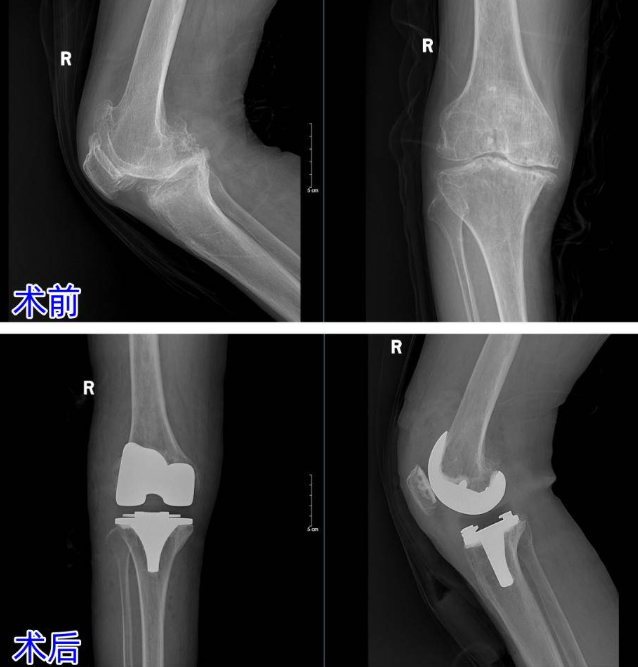

20年膝痛难忍致畸形 南郊骨科杨学良主任妙手置换解痛苦

66岁张阿姨(化名)右膝疼痛20多年,起初久走隐痛,后发展成严重膝内翻畸形,关节僵硬,下蹲、起身困难。口服药物、外用膏药效果不佳。她慕名到济南南郊医院骨科,杨学良主任确诊为骨性关节炎4级,给出方案——全膝关节置换术可解决问题。

术中,杨主任用独创的内侧副韧带深度松解技术精准平衡关节间隙,安装假体后即刻矫正畸形。

术后3天,老人膝关节活动度接近正常,能轻松迈步。膝关节骨性关节炎是中老年人“隐形杀手”,拖得越久畸形越重。杨主任提醒,早诊早治是关键,晚期严重畸形患者,人工关节置换可快速“重启”关节功能,告别疼痛束缚。